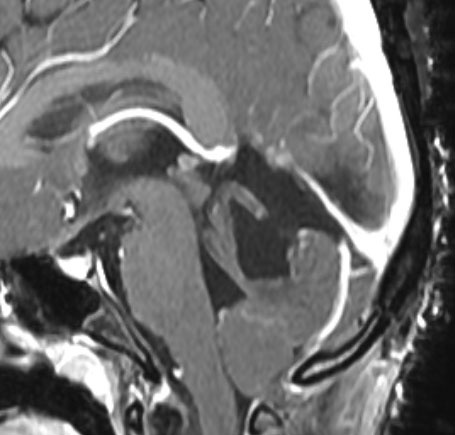

小脳毛様細胞性星細胞腫のFLAIR画像所見

壁在結節を伴うのう胞性小脳毛様細胞性星細胞腫は,結節を手術摘出すれば治癒するものです。しかし,あたかも腫瘍が残っているようなMRI画像所見が残ることがあります。

この例は,10歳の子どもに無症状で偶然発見された大きなのう胞性小脳毛様細胞性星細胞腫です。開頭手術で腫瘍結節は全摘出して腫瘍のう胞は縮小したままです。(画像はクリックすると拡大して見えます)

開頭手術で白く増強される結節部分だけを摘出しました。MIB-1はやや高値で3%と報告されました。病理組織診断は,WHO grade 1 毛様細胞性星細胞腫です。

6年後のMRI FLAIR画像です。摘出腔周囲の高信号域が残存しています。ここまで残ると腫瘍周辺浮腫ではありませんし,腫瘍細胞が左小脳半球に広範囲に浸潤して残存しているものだと判断されます。しかし,6年間で病変の増大傾向がありませんでした。この残存腫瘍(らしい所見)に対して放射線治療や化学療法を行うべきかどうか,結論は出ていません。しかし,経過観察を続けても増大して来ない例があることは確かです。一方で,この高信号領域が拡大したり,ガドリニウム増強される病変が再出現して治療がまた必用となることもあります。